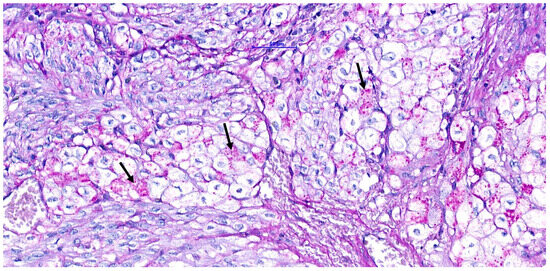

Ultrasound, Histomorphologic, and Immunohistochemical Analysis of a Cardiac Tumor with Increased Purkinje Cells Detected in a Canine Fetus 42 Days into Pregnancy

2.2. Histopathology, Histochemical, and Immunohistochemical Studies